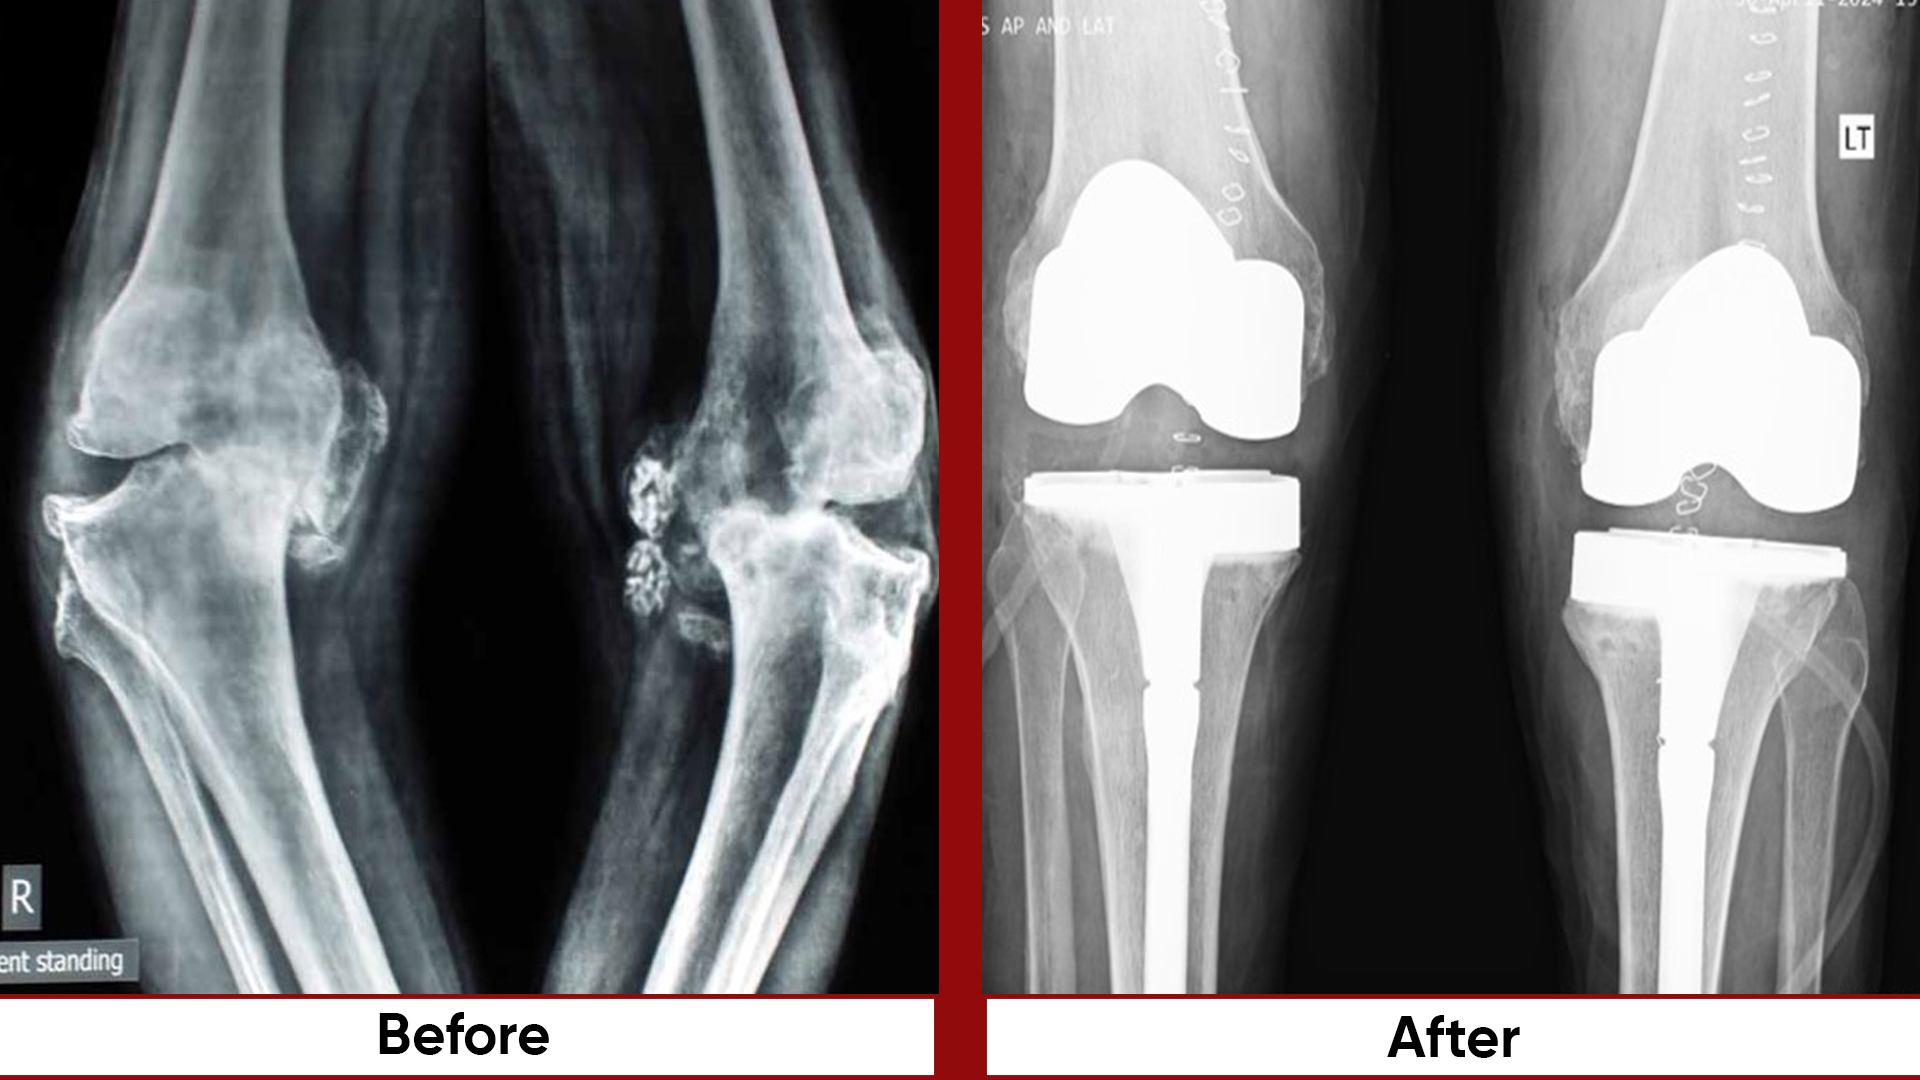

• Total Knee Replacement (TKR)

• Total Hip Replacement (THR)

• Deformity Correction (limb lengthening, bowlegs, knock knees)

• Osteotomies (bone realignment surgeries)

• Arthroplasty